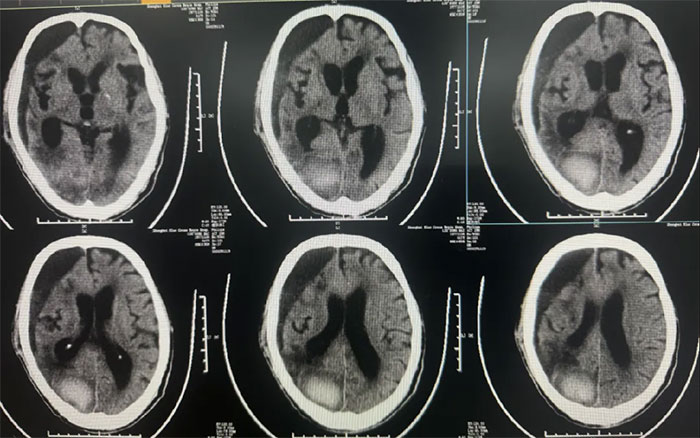

● 硬膜下血肿引流15天后拔管,中线基本复位,硬膜下血肿较前明显减少;

● 患者神志昏迷,自动睁眼,无发声,肢体刺痛躲避。GCS评分:9分;

● 无明显颅内感染,生命体征平稳。